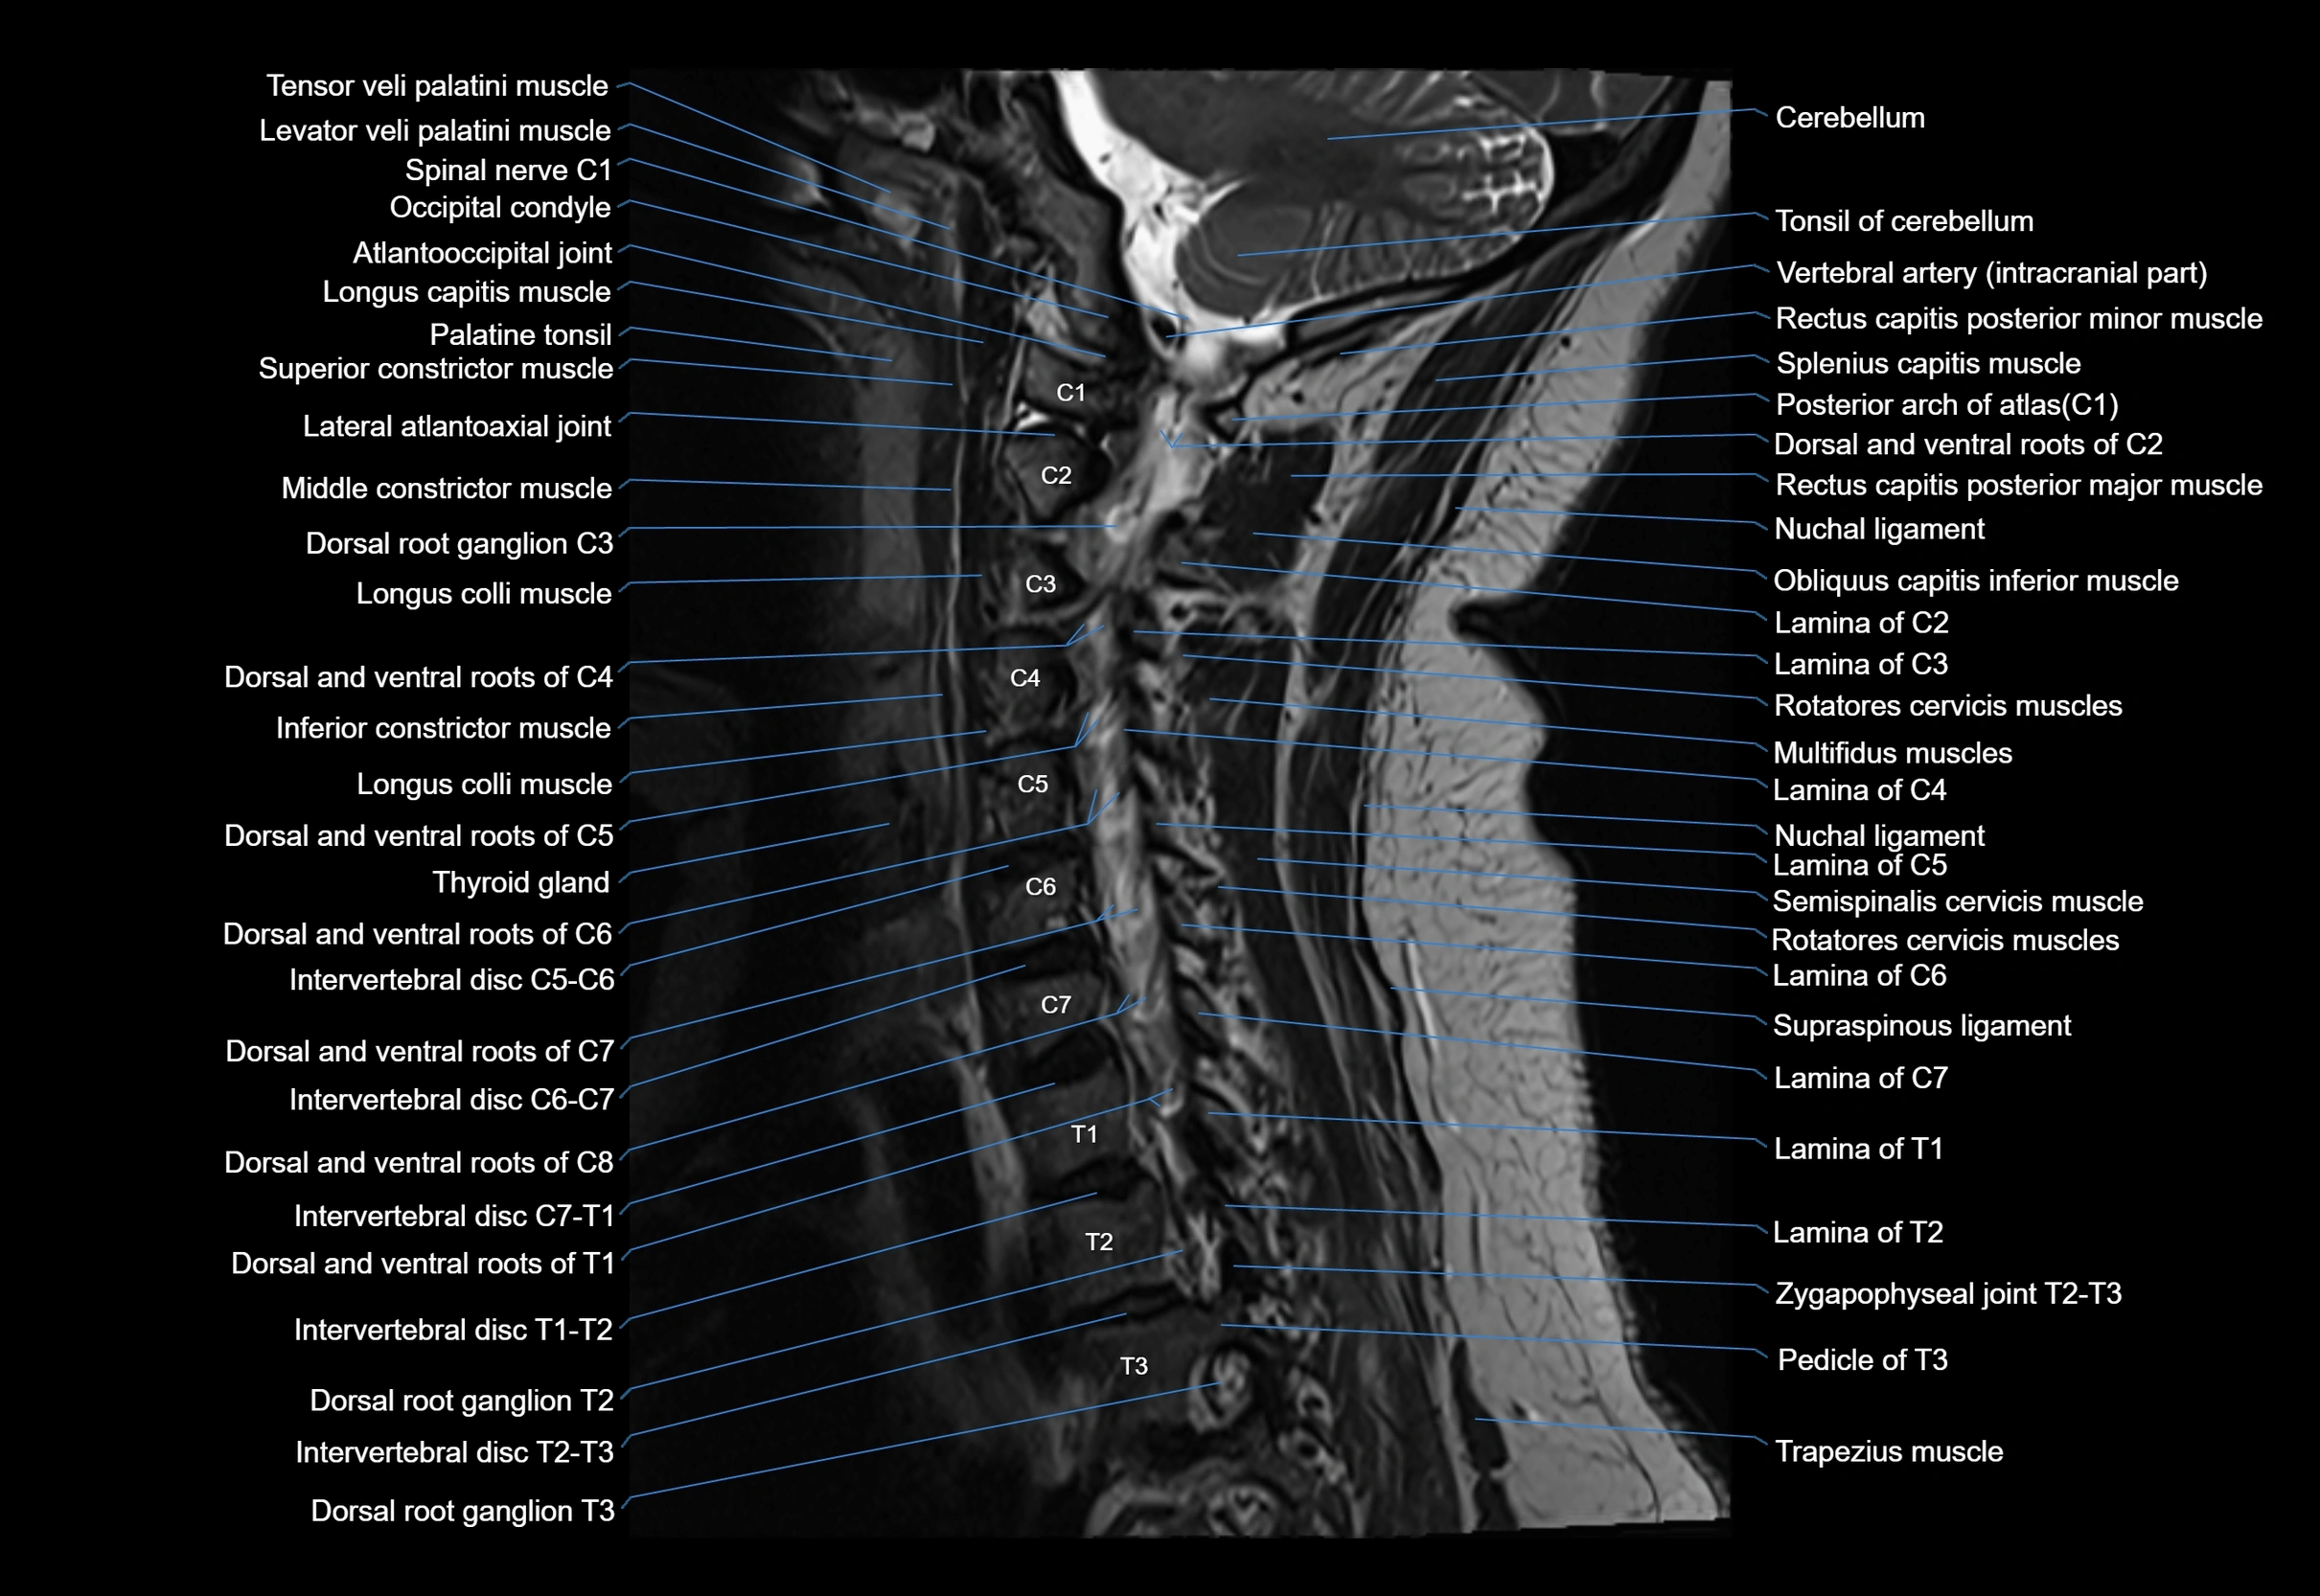

MRI appearance

T1-weighted images:

• Annular epiphysis: Low signal cortical rim at the vertebral margin

• Adjacent marrow: Intermediate-to-high signal in the vertebral body

• Disc interface: Clear delineation between bone and annulus

T2-weighted images:

• Annular epiphysis: Low signal intensity line

• Endplate cartilage (in younger patients): Intermediate signal

• Intervertebral disc: High signal nucleus pulposus

STIR:

• Annular epiphysis: Low signal cortical rim

• Adjacent marrow: Suppressed fat signal with preserved bony outline

• Utility: Highlights marrow and endplate interface in developing spine

MRI image

image